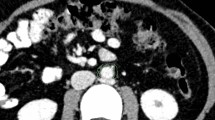

Metabolic profiling of bone marrow of lumbar vertebra 7

LC-MS was performed on the bone marrow of lumbar vertebra 7 in all experimental rabbits. The principal component analysis(PCA)and partial least squares discriminant analysis (PLS-DA) plots show that show the tendency for the diabetic group to be separate from the control group (Fig. 2). The R2 of the PLS-DA model was 80%, while the Q2 of the PLS-DA model was 10%. Based on variable importance in the projection scores > 1 and fold change scores > 2 or < 0.5, we screened 36 differential metabolites in Fig. 3. Pathway analysis was performed using enrichment analysis and topology analysis to identify differential metabolic pathways. As summarized in Table 3, the differential metabolic pathways related to bone marrow microvascular changes included linoleic acid metabolism, arachidonic acid metabolism, fatty acid biosynthesis, fatty acid elongation, fatty acid degradation, histidine metabolism, beta-alanine metabolism, alpha-linolenic acid metabolism, glycosylphosphatidylinositol-anchor biosynthesis, purine metabolism, and glycerophospholipid metabolism. These results suggest a significant perturbation in lipid fluxes. Because the p-value of linoleic acid metabolism is low, which indicated statistical significance, and the impact score is high, we then focus on linoleic acid metabolism. Five differential metabolites, including four phosphatidylcholines (PCs) and one fatty acid, were related to linoleic acid metabolism and were selected for further correlation analysis. They were PC 14:0–16:0, PC 15:0–18:1, PC 18:0–20:2, PC 18:1–20:1, and FA 18:2.

Metabolomic analysis and identification of differential metabolites. PCA and PLS-DA plots show the tendency for the diabetic group (Dg, green circles and green ellipses) to be separate from the control group (Cg, red circles and red ellipses) (2a, b). A volcano plot showing the distribution of all and differential metabolites based on their fold-change values (x-axis, logarithmic scale) and p-values (y-axis, logarithmic scale) (2c)

Summary of all 36 differential metabolites, their respective fold-change values and VIP as calculated by R studio. Each red and green dot represent the diabetic group and the control group, respectively. The average fold-change and VIP of each metabolite in diabetic group or the control group is denoted by a vertical line